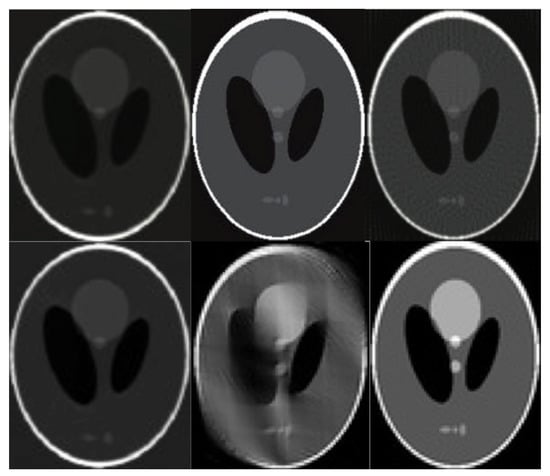

3. Computed Tomography Imaging Speeding Up

4. Compressively Sensed CT/PET Signals

6. Evaluation

7. Results